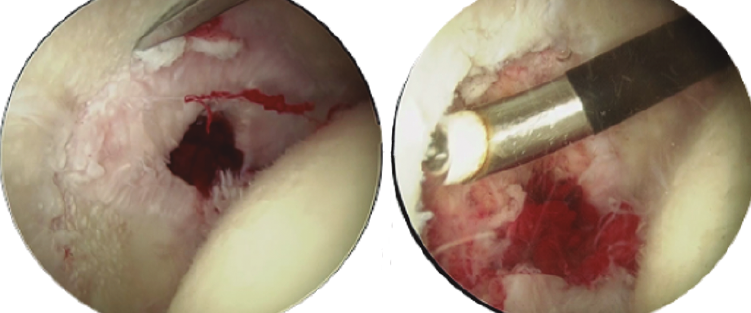

Un gesto añadido que podemos hacer, sin conocer exactamente la repercusión clínica del mismo, es la retirada del osteofito central con fresas o material cortante curvo (Figura 4).

Figura 4. Paciente con osteofito central acetabular (imagen izquierda). Resección del osteofito central (imagen derecha).